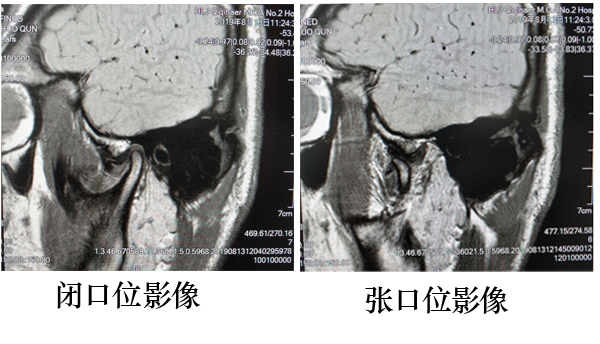

目前MRI作为颞下颌关节功能紊乱综合征(TMJDS)的首选检查已经得到广泛的认可,其优势为:一、无创、无电离辐射;二、软组织分辨率高,任意角度成像,对于关节盘的移位、变形,关节面的退行性变,滑膜病变、关节积液、关节周围软组织的病变均能很好的显示。三、通过闭口位及张口位扫描的图像对比,明确移位关节盘能否自行复位。

可复性关节盘前移位